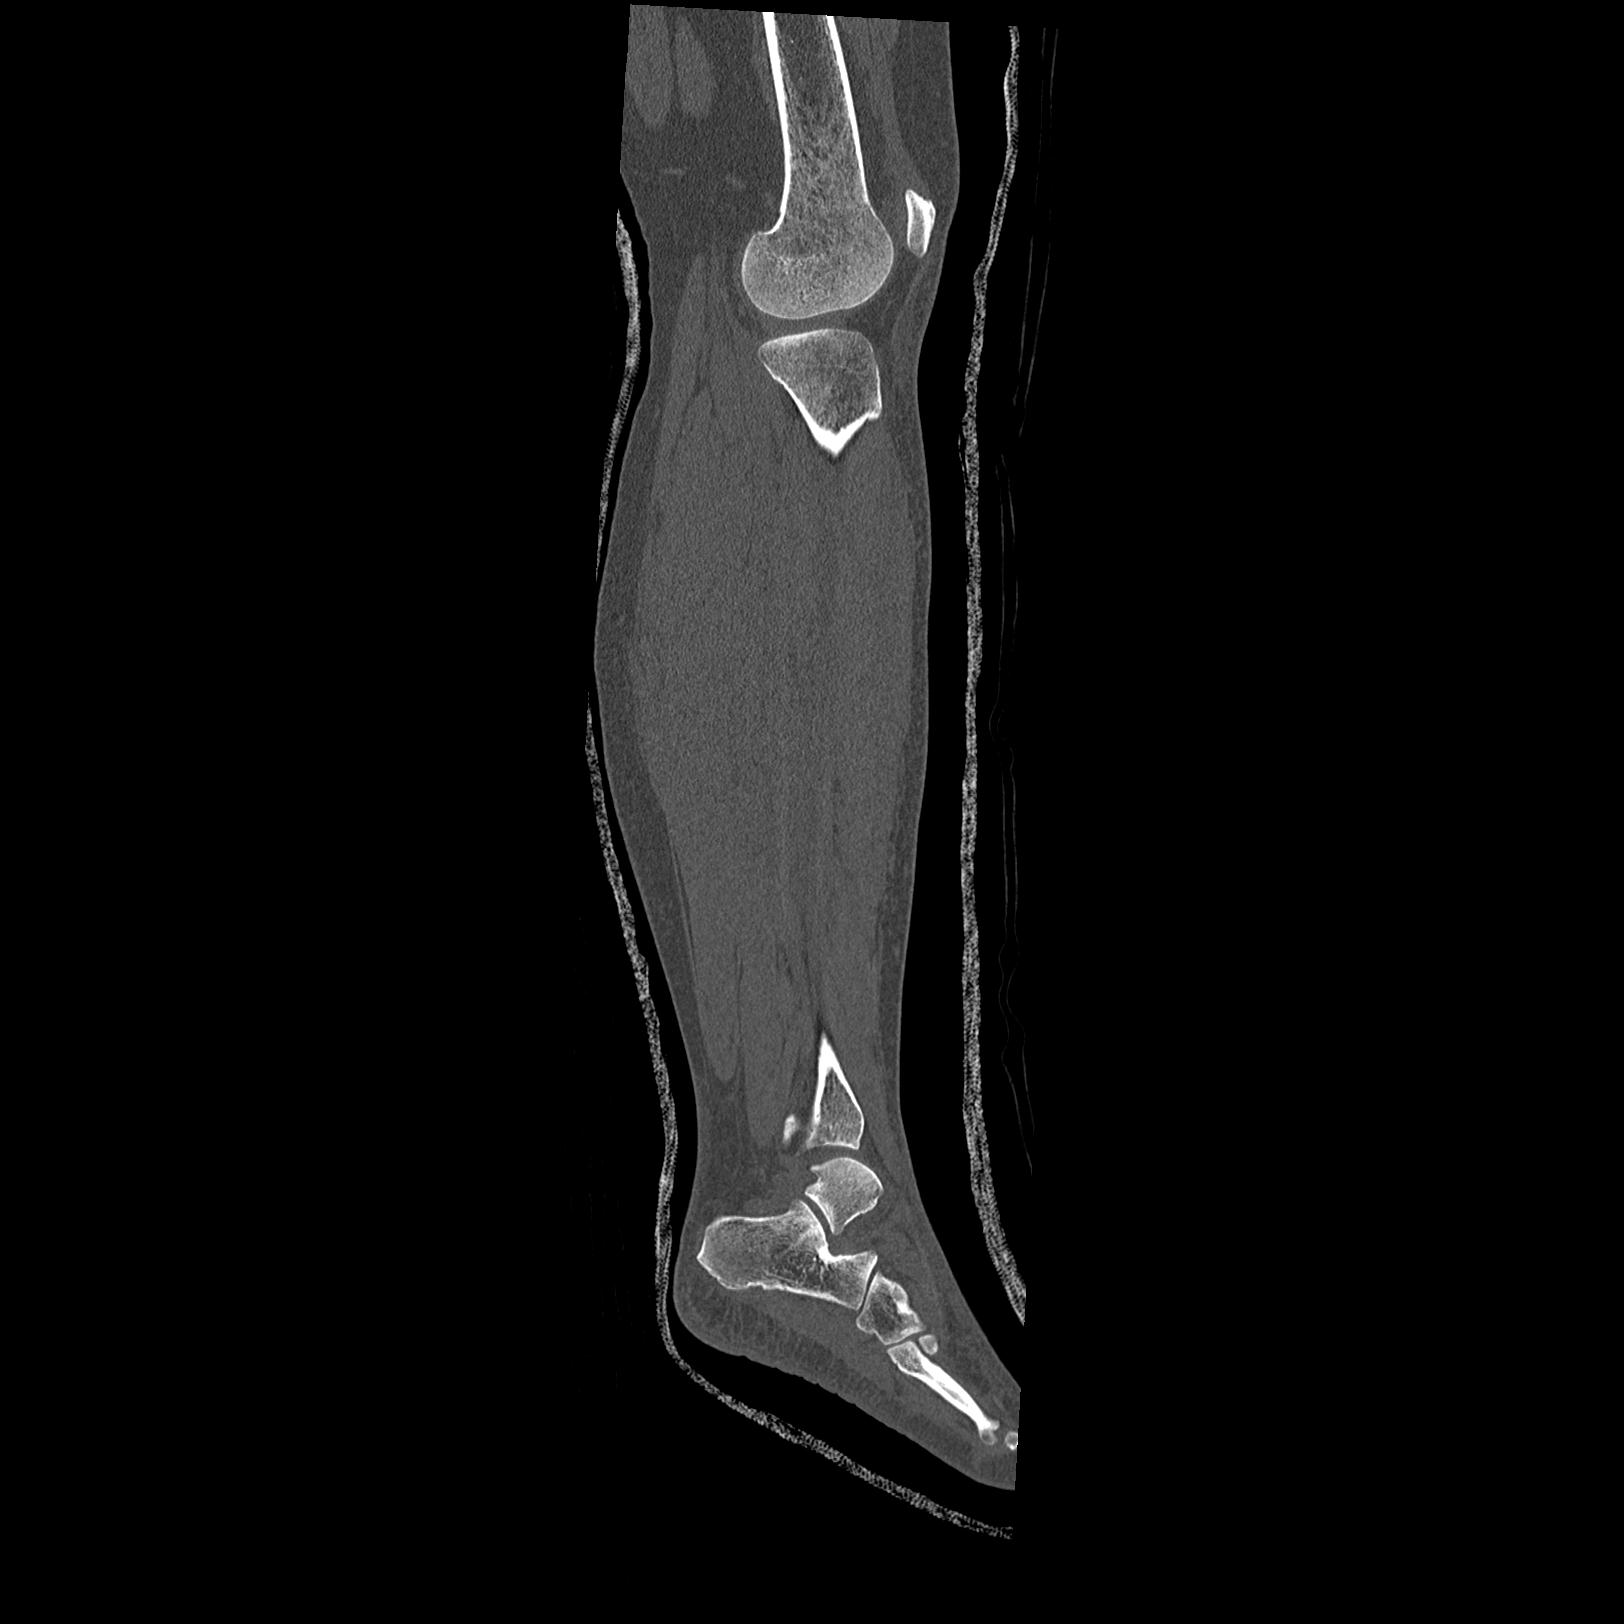

102803 1/12(キウスなし) 1/27 左下腿 4R 30歳女性 左脛骨軸内釘